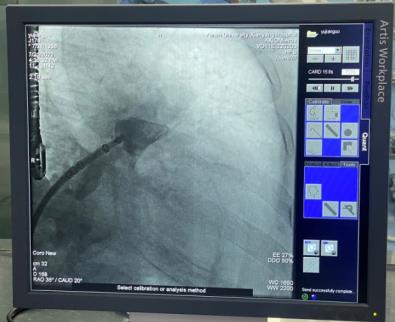

穿刺房间隔后置入6F猪尾导管,于CAU20°,RAO35°进行左心耳造影,可见左心耳为大角度反鸡翅形,测量左心耳开口26mm,深度25mm。各位在线的专家有张玉顺教授、宋治远教授、胡浩教授等,进行了热烈讨论后,一致认为该例手术难度较大,封堵伞不易释放。

经过仔细读图,发现左心耳下叶可作为封堵主轴向,该方向避免了大角度反折,但深度略浅,手术难度仍是不小。最终选取30mmWATCHMAN封堵器。

术中我们介入团队熟练配合,封堵器精确定位,完美释放,食道超声证实定位准确,压缩比20%,牵拉实验封堵器无移位,锚定牢靠,符合PASS原则。释放后造影证实封堵器完全封闭左心耳,超声示无残余分流。